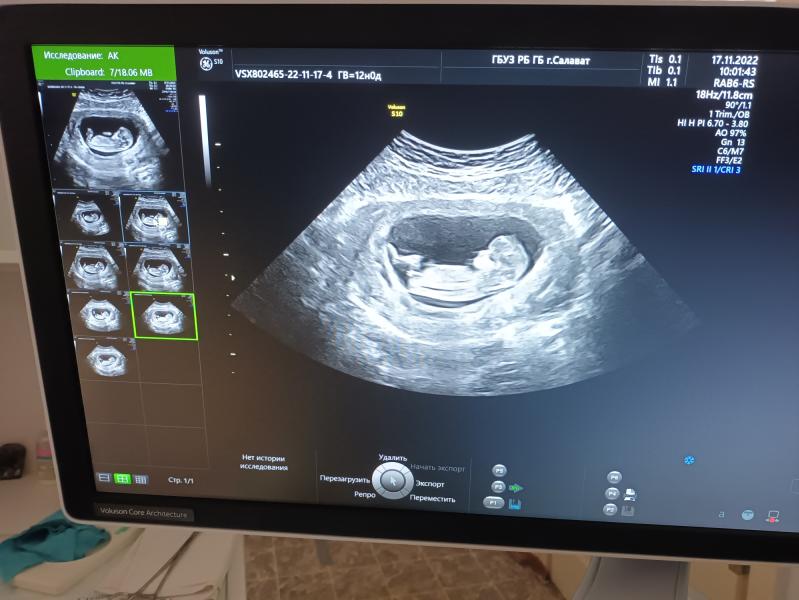

Сегодня была на первом скрининге (12 недель)

Какое чёткое изображение, видимо аппарат УЗИ хороший очень. У нас такого нет, увы